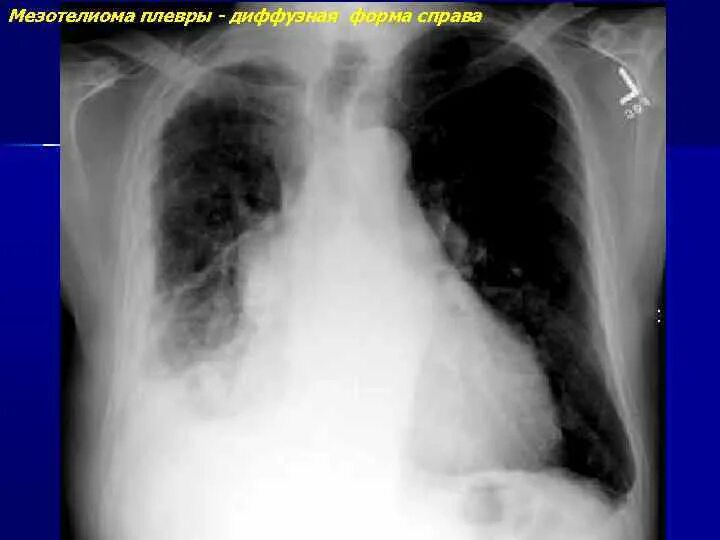

Метастазы плевры